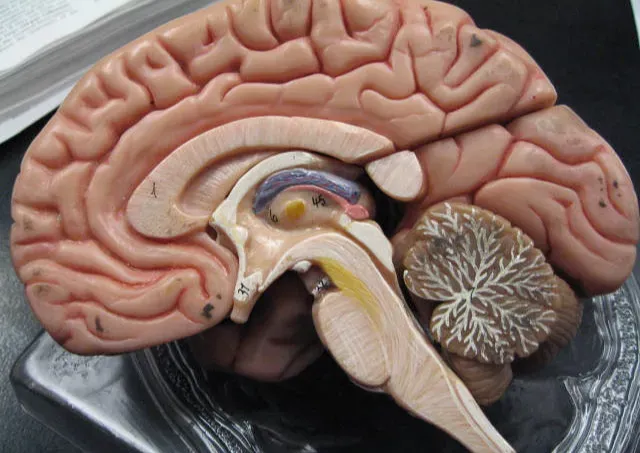

One of the most grounded explanations for déjà vu starts in the hippocampus, the brain structure deeply involved in forming and retrieving memories. When you walk into a new room, your brain rapidly compares what you’re seeing to a vast library of stored scenes and experiences, like a search engine trying to find a match. Déjà vu seems to happen when this comparison system temporarily misfires, giving you the feeling of recognition without an actual memory to back it up.

Researchers who study memory often talk about two things: familiarity and recollection. Familiarity is that gut sense that something “rings a bell,” while recollection is the detailed memory – when, where, with whom. In déjà vu, familiarity kicks in strongly, but recollection is empty; your brain screams “I know this,” and at the same time admits, “I have no idea from where.” That broken pairing – strong familiarity, zero detail – is at the heart of the experience.

Some of the strongest clues about déjà vu come from people with temporal lobe epilepsy. Many of them report intense déjà vu right before a seizure, almost like a flashing warning light from the brain. When doctors stimulate specific areas of the temporal lobe during surgery, patients sometimes spontaneously report that strange “this has happened before” feeling, even in a bare operating room with nothing special going on.

This does not mean that people who get typical déjà vu have epilepsy, but it suggests that similar circuits are involved. The temporal lobe, especially near the hippocampus, seems to be crucial for that mix of familiarity and memory. In healthy brains, these circuits normally keep things clear: what’s new, what’s old, what’s similar. When they briefly misfire – not enough to be dangerous, just enough to be noticeable – you might end up with a short, harmless echo of the kind of strange familiarity that in epilepsy can be much more intense.